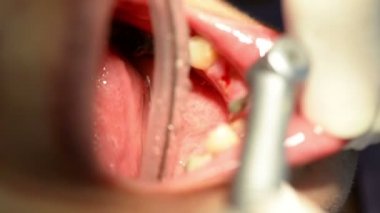

Yakın plan, dişçi diş tedavisinden önce kadın bir hastaya anestezi enjekte eder..

Eser Sahibi: Denys Diedov